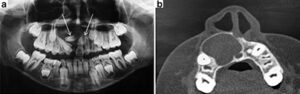

Los estudios de imagen (radiografía panorámica y tomografía computarizada) revelaron la presencia de dos dientes supernumerarios retenidos localizados en la región anterior maxilar, uno de los cuales estaba asociado a una radiolucidez unilocular, involucrando su corona y provocando desplazamiento de los dientes 11, 12 y 13 hacia la porción distal (figuras 2a y b)

Figura 2. a) Radiografía panorámica donde se aprecia lesión radiolúcida y presencia de dientes supernumerarios amorfos (flechas). Nótese la retención del incisivo lateral superior derecho. b) Tomografía computarizada en cortes axiales presentando una extensa área hipodensa con perforación de corticales.